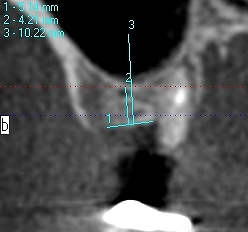

術前術後のCTになります

術前術後のCTになります